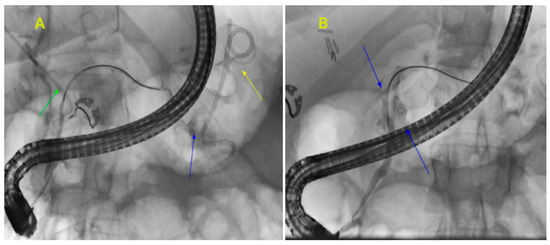

3.3. Transpapillary Gallbladder Drainage (ETP-GBD)

3.4. Endoscopic Ultrasound-Guided Gallbladder Drainage (EUS-GBD)